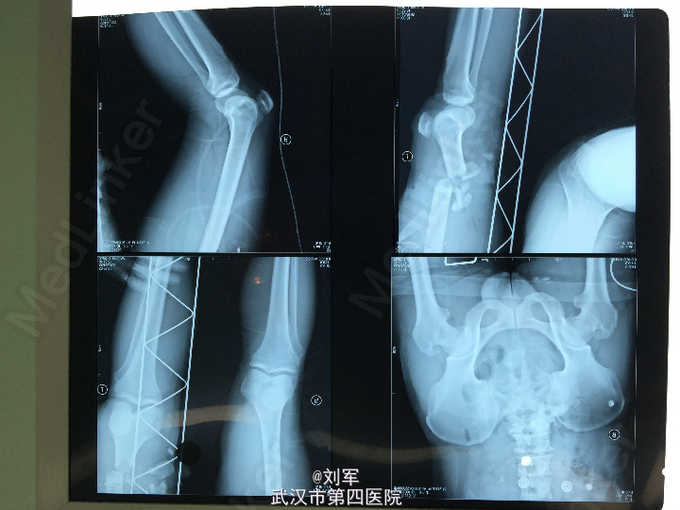

患者,朱某,男,51岁。因“外伤后左大腿出血、疼痛、畸形2.5小时”入院。两个半小时前,患者左大腿被中午砸伤,当即出血、感疼痛明显,畸形,伴活动受限。伤后被同事送入我院诊治,门诊行拍片及抽血检查后,送入手术室。起病来,神志清,无昏迷、恶心、呕吐及大小便失禁史。

查体:左大腿下段内侧可见不规则伤口,创面内可见内侧肌群断裂、外露,污染明显出血。左大腿畸形,可触及骨擦感,压痛。左小腿及足部皮温低,苍白,未能触及足背动脉及胫后动脉搏动。针刺趾腹未见出血,足背感觉缺失。入院X线片:左股骨下段粉碎骨折、骨缺损。

入院后,申请血液,急查左下肢动脉彩超:左侧股动脉下段断裂、栓塞。急诊麻醉下行清创+大隐静脉移植修复股动脉术+股骨复位外固定架固定术。